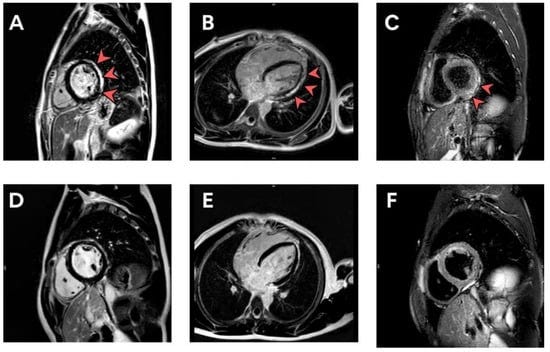

Figure 2. (A–F) cMRI illustrating LGE in a patient with subacute myopericarditis at the time of diagnosis (A–C) and 5 months post-diagnosis (D–F). cMRI, cardiac magnetic resonance imaging; LGE, late gadolinium enhancement.

Myopericarditis was confirmed in one patient after vaccination.

Two patients had suspected pericarditis and four patients had suspected subclinical myocarditis.